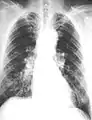

The abnormal chest x-ray and its interpretation remain the most important factors in establishing the presence of pulmonary fibrosis.[11] The findings usually appear as small, irregular parenchymal opacities, primarily in the lung bases. Using the ILO Classification system, "s", "t", and/or "u" opacities predominate. CT or high-resolution CT (HRCT) are more sensitive than plain radiography at detecting pulmonary fibrosis (as well as any underlying pleural changes). More than 50% of people affected with asbestosis develop plaques in the parietal pleura, the space between the chest wall and lungs. Once apparent, the radiographic findings in asbestosis may slowly progress or remain static, even in the absence of further asbestos exposure.[25] Rapid progression suggests an alternative diagnosis.

61-year-old working industrially with asbestos for decades